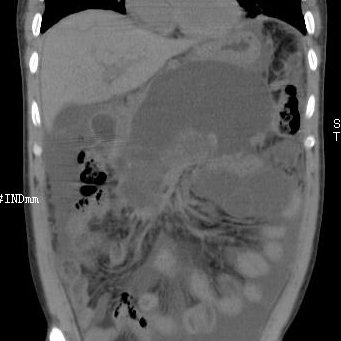

2021年1月底在家人的陪同下蒲某就诊遵义市第五人民医院,以急性胰腺炎并发假性囊肿形成收入普外科治疗。入院时,患者严重贫血、营养不良、电解质代谢紊乱、腹腔积液、胰腺假性囊肿形成,张丰深主任、孙海主任的普外科团队及时给予患者抑制胰酶分泌、肠内外营养支持、多次胸腹腔穿刺引流等治疗,其贫血情况、营养状态得到显著改善,但复查腹部影像显示胰腺假性囊肿较入院时变化不大。

经过充分的术前准备,在麻醉科、介入室的配合下,3月11日由陈达凡主任及消化内科团队为患者实施了超声内镜引导下胰腺巨大假性囊肿支架置入引流术。手术中,首先通过超声内镜寻及胰腺假性囊肿,发现病灶多处局部血供丰富,如操作不慎,即有发生大出血的可能。针对此情况,超声内镜正可发挥优势,其多普勒显示功能对血流具有敏锐探查能力,在它引导下避开血管,选择了最佳的引流部位。在穿刺针进入囊腔后,应用专门电切装置,依次切开胃壁、囊腔壁,并进行瘘管扩张,可见大量囊液流出。为保证囊液的流出持续通畅,置入了双支架进行引流。整个手术过程创伤小,基本没有出血,且在全麻状态下施行操作,患者没有痛苦感受,术后第二天便可做床边一般活动及逐渐恢复饮食。

目前,经消化内科医护团队的精心治疗,医院多个科室的大力支持,患者精神状态佳,腹部症状得到缓解,复查CT显示假性囊肿明显缩小,病情逐步恢复。